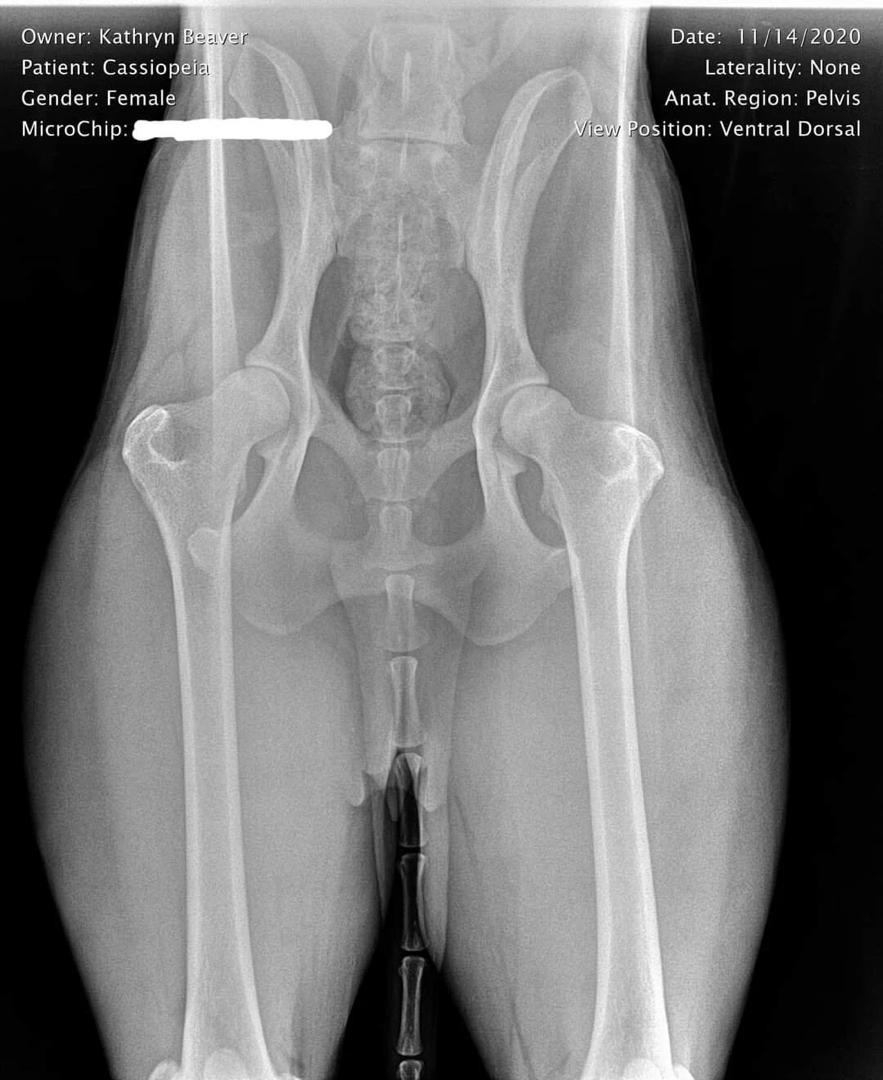

Cassie Hip X-Ray

Hip X-Ray Results

OFA Hip Evaluation: Good